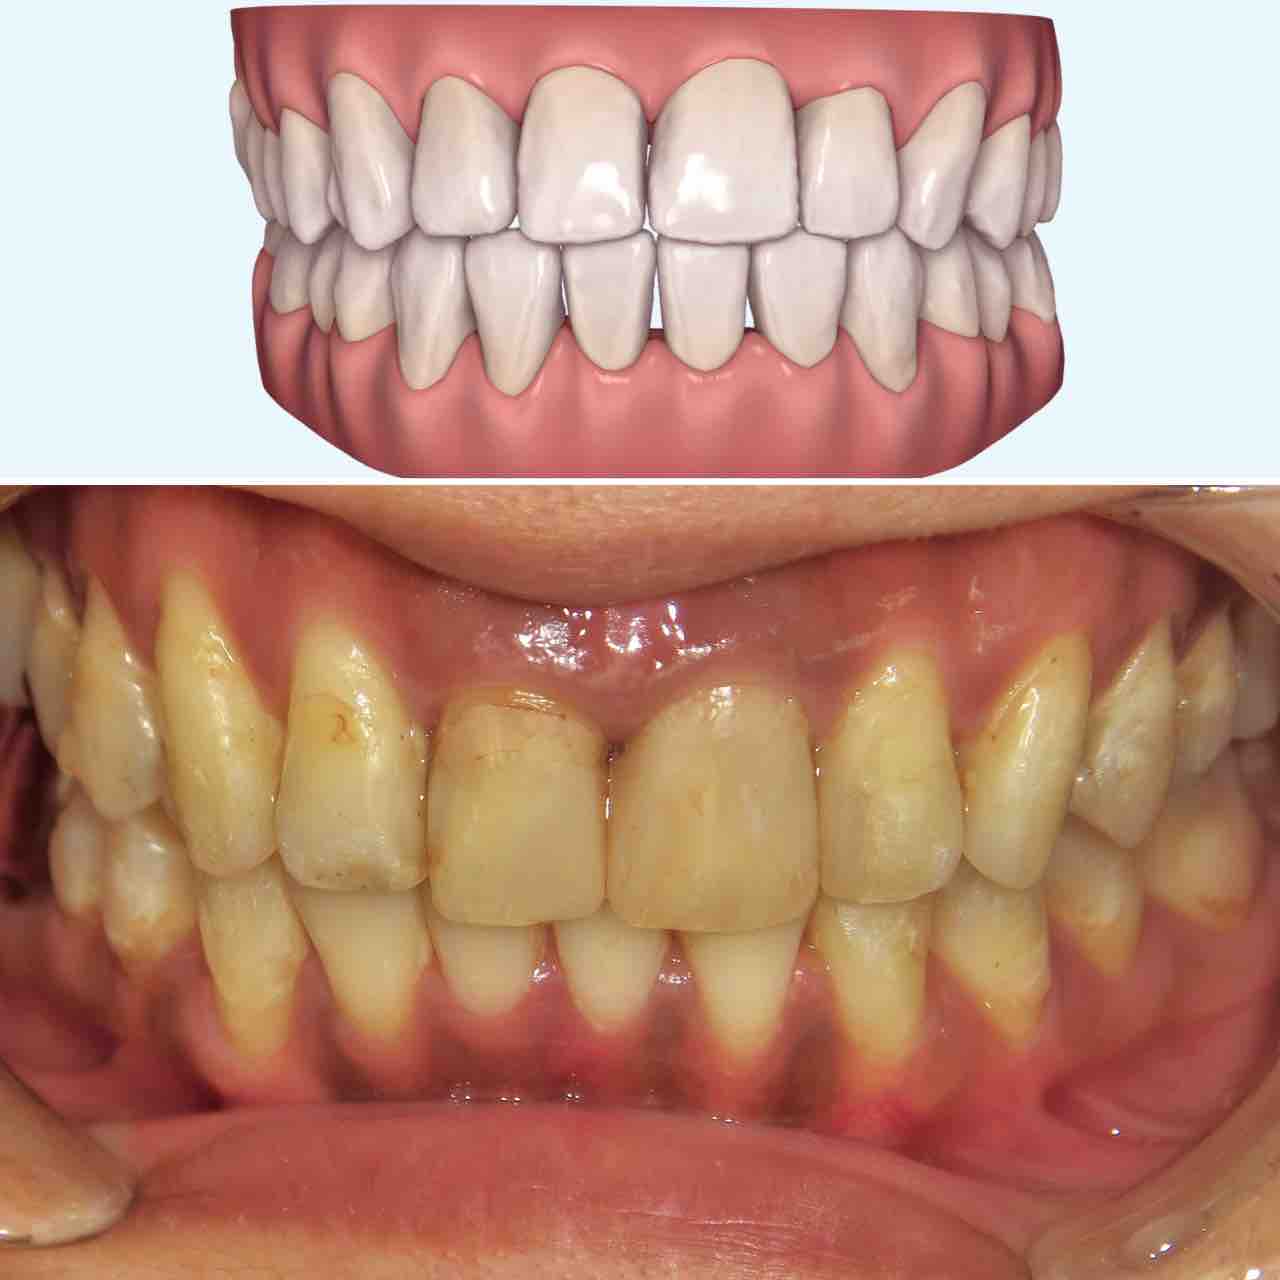

横から見ると少し前歯が出っ歯気味になっている。

横からは、やや出っ歯だったのが、出っ歯感はなくなった。

噛み合わせの比較。